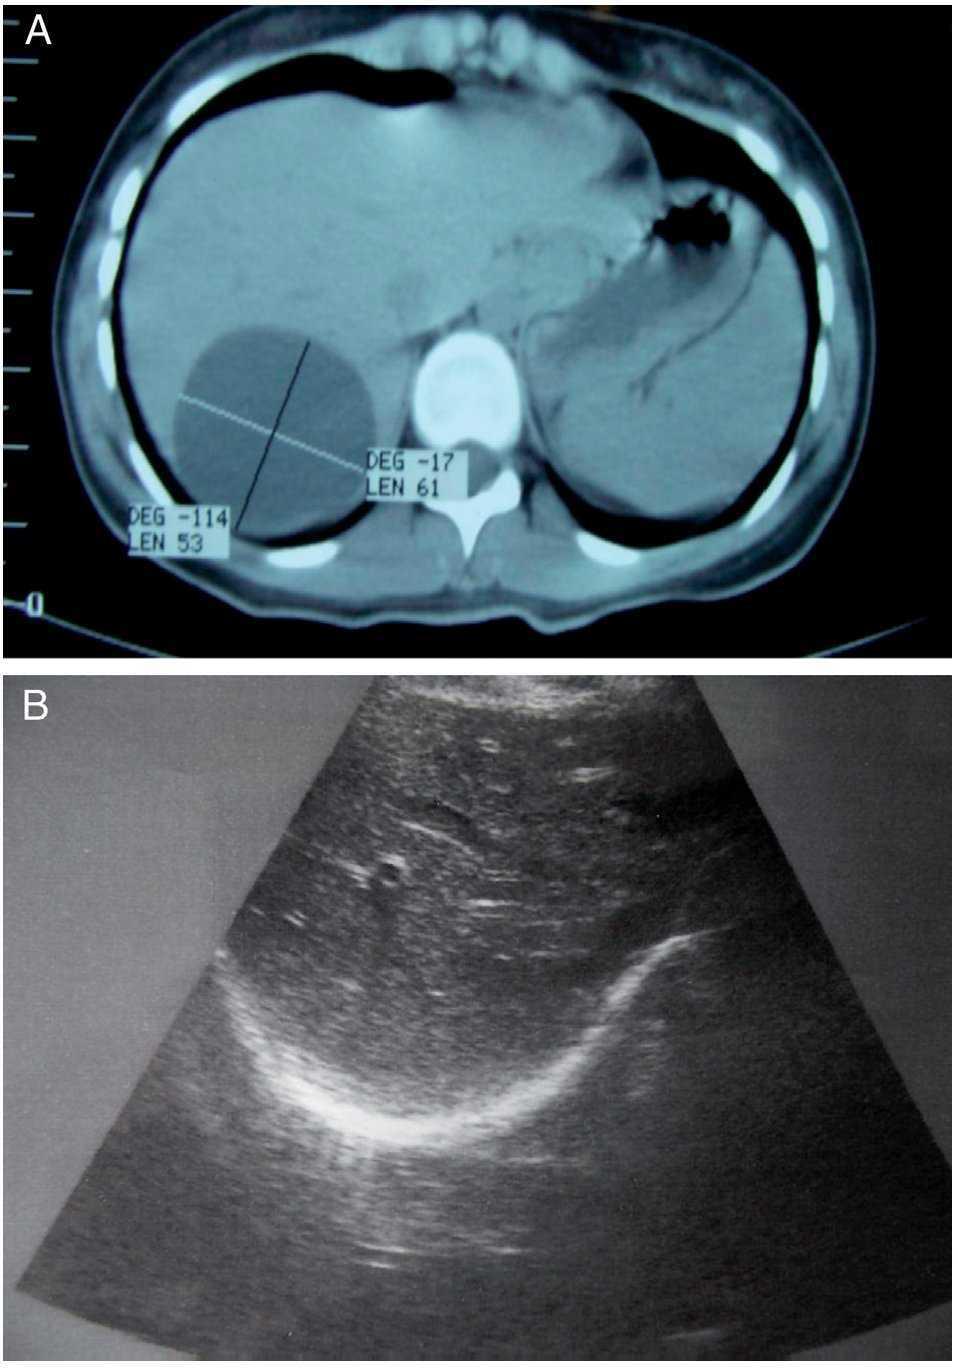

A 16-year-old female had disease onset in Januar y 2011 with mild pain in the right hypochondrium for which her attending physician ordered an ultrasound study. It revealed the presence of a rounded anechoic image of approximately 6 cm in diameter in segment VII of the Couinaud liver segment classification. Upon hospital admittance, her basic laboratory work-up (full blood count, blood chemistry, and coagulation tests) was normal. Eosinophils were reported at 0% and it was not possible to order other tests. The patient underwent laparoscopic exploration on January 27, 2011, during which the cyst could not be visualized because of its posterosuperior location. Two weeks later, with the patient experiencing an intensified dull pain that did not allow her to eat properly, another ultrasound study was ordered along with an abdominal computed axial tomography scan, correctly locating the cyst in segment VIII of the Couinaud classification (Figs. 1A-B).

Figure 1. A) Absence of septums in the interior of the simple biliary-like cyst. B) Postoperative ultrasound control showing the absence of cysts.